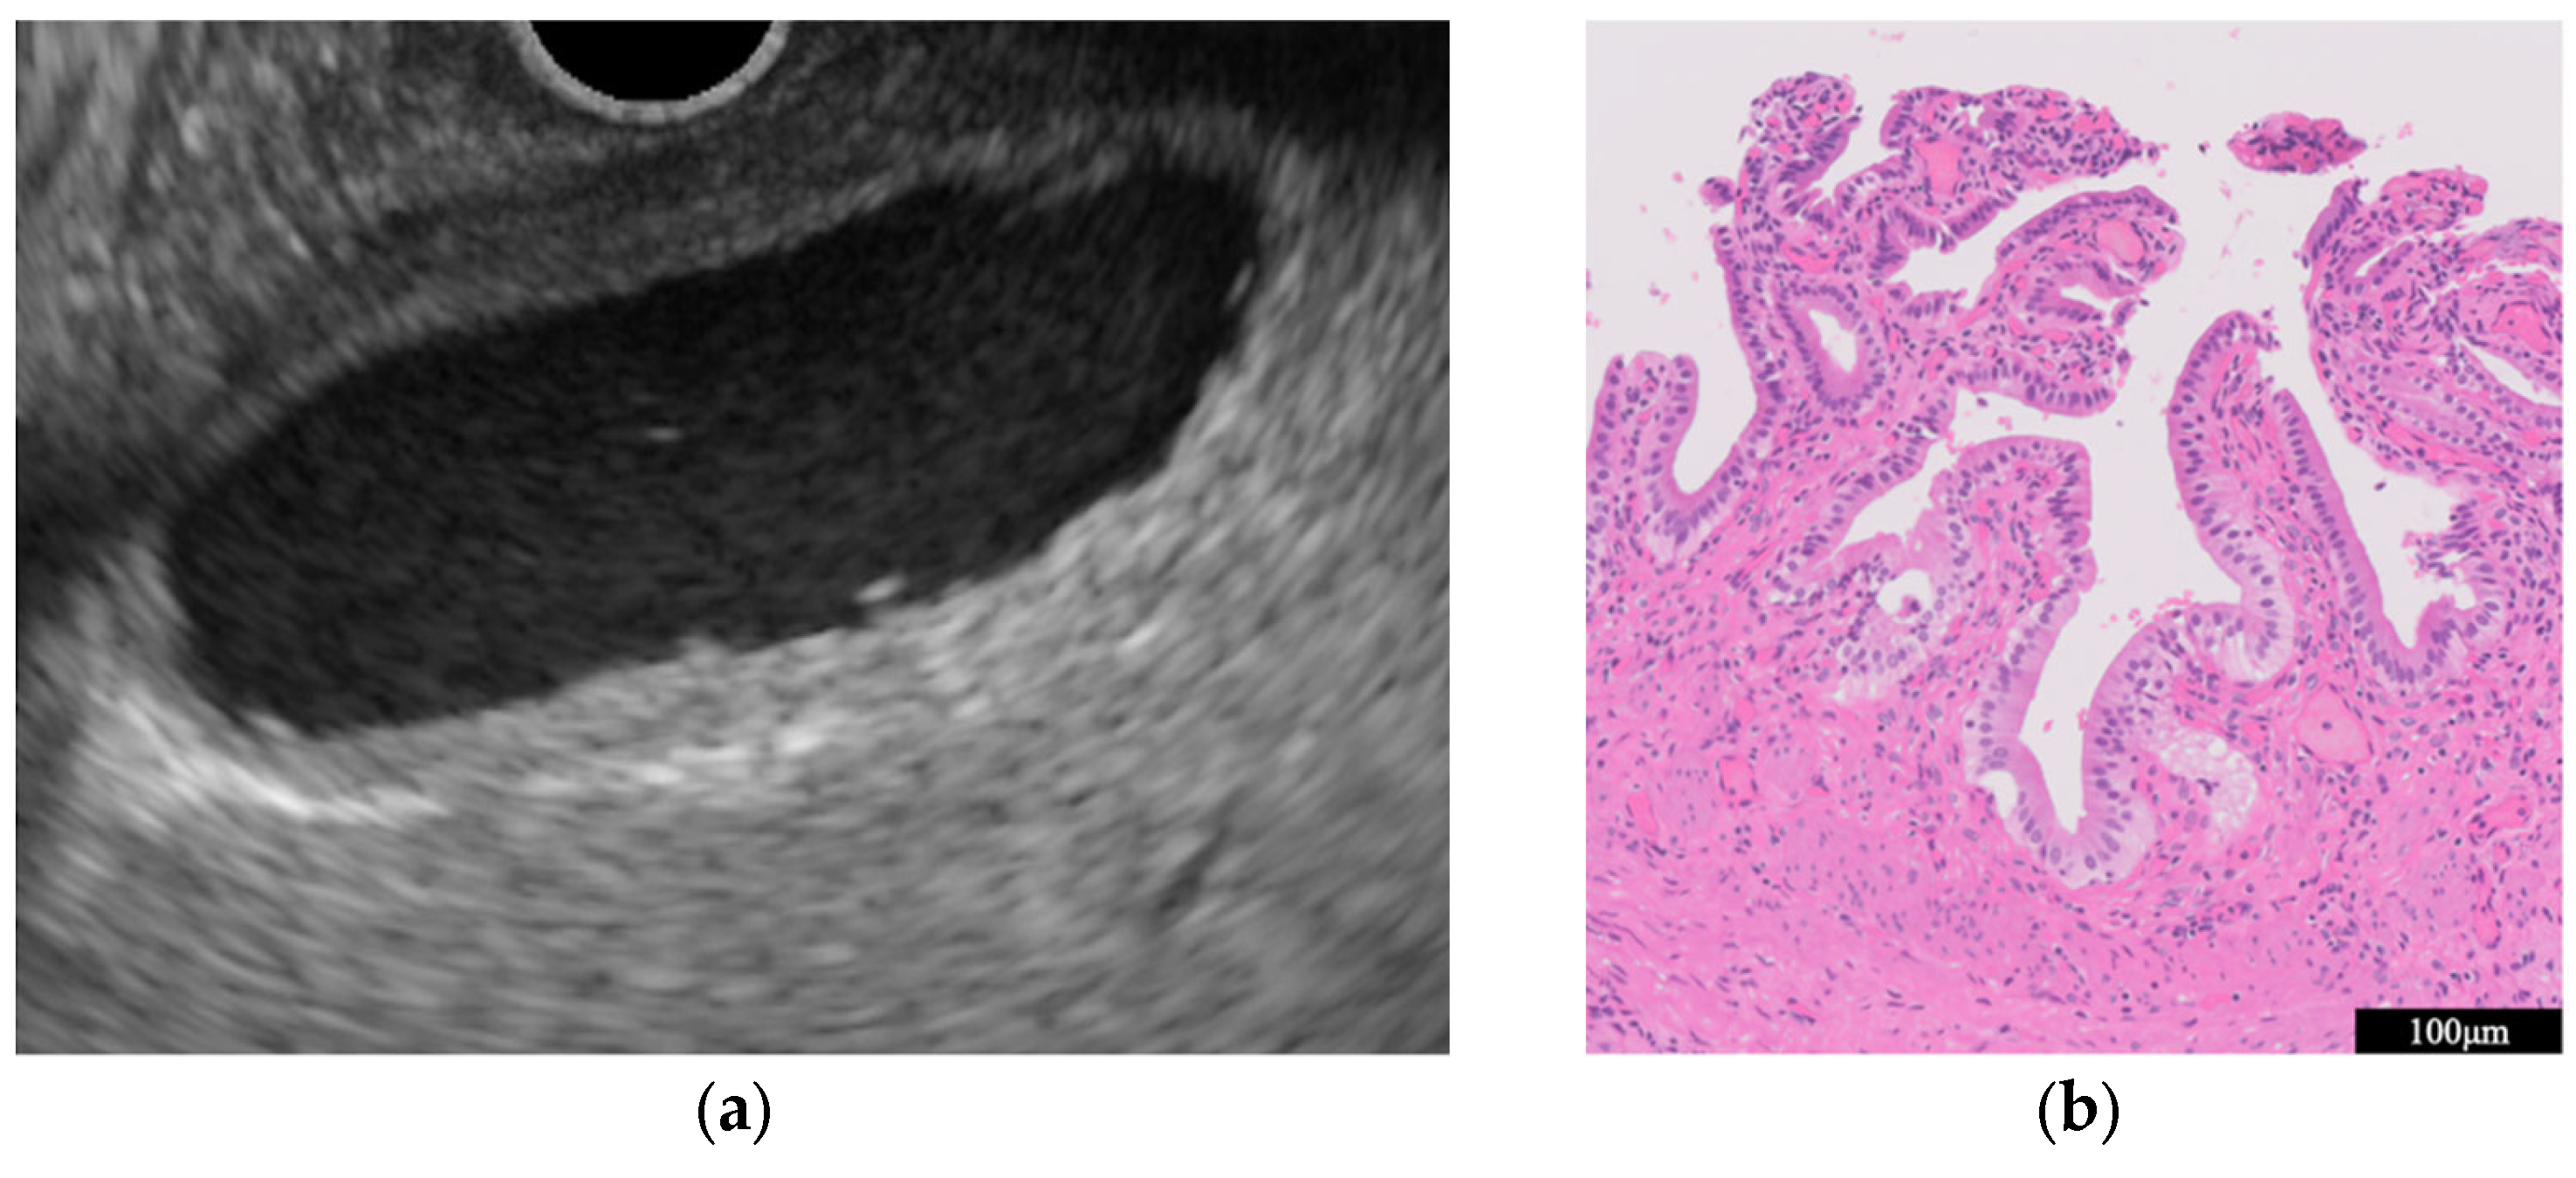

- Immunoglobulin G4-related sclerosing cholecystitis (IgG4-CC) (Figure 3)

- GB mucosal hyperplasia associated with pancreaticobiliary maljunction (PBM) (Figure 4)